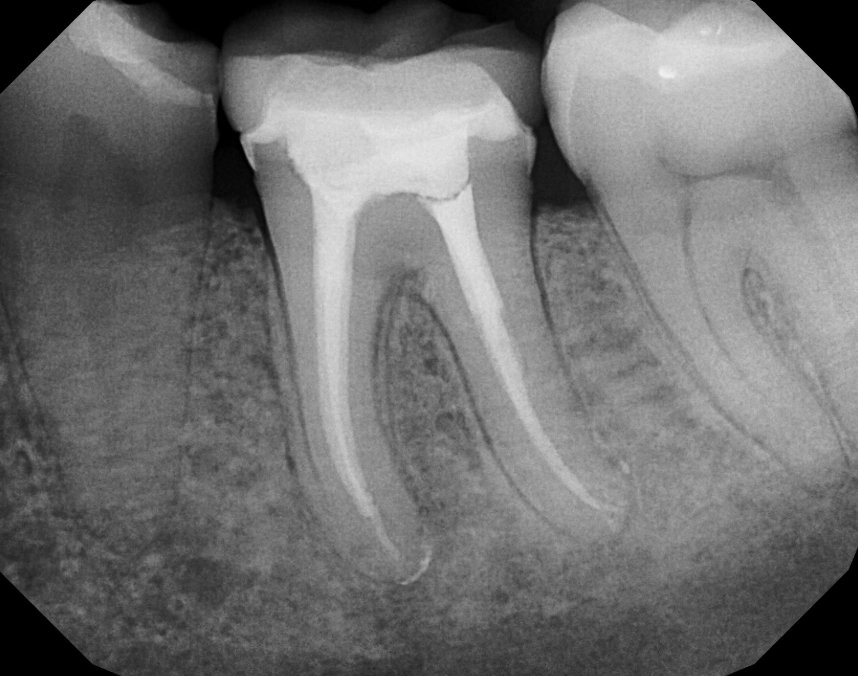

Disinfection and Filling: The canals are flushed with antimicrobial solutions. Once dry, they are filled with a rubber-like material called gutta-percha, sealed in place with a biocompatible cement. The goal is to hermetically seal the space to prevent re-infection.

The Temporary Fill: The access hole is closed with a temporary filling. The entire process for a premolar typically takes 60 to 90 minutes, sometimes split over two visits if there's a significant infection that needs time to drain.

For almost every premolar, you will need a dental crown. This cap encases the entire tooth, protecting it from fracture and restoring its function for chewing. Sometimes, if a lot of tooth structure is missing, a post may be placed inside the canal to help anchor the crown. Don't delay this step. Schedule your crown appointment within a few weeks of the root canal.